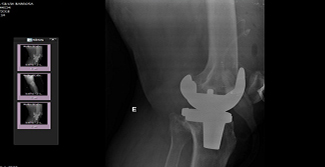

Foi realizada nesta quarta-feira, 24 de agosto, a primeira videorreunião entre o Grupo Hospitalar Conceição (GHC) e o Hospital de Clínicas da Universidade Federal de Uberlândia (HC-UFU), de Minas Gerais, para troca de conhecimentos sobre o controle e uso de órteses e próteses. O GHC, referência no país no assunto, foi convidado pelo hospital mineiro, que busca subsídios para aprimorar os controles existentes no HC-UFU.

Gestor do Controle de Órteses e Próteses do Hospital Cristo Redentor, Juarez Correa Fraga, que participou da videorreunião, disse que o HCR se destaca nessa área uma vez que realiza o recebimento e a dispensação de materiais com controle total de rastreabilidade.